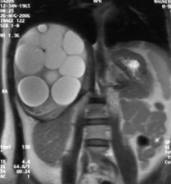

Как выглядит эхинококк (фото)?

Срез компьютерной томографии печени с эхинококковой кистой.